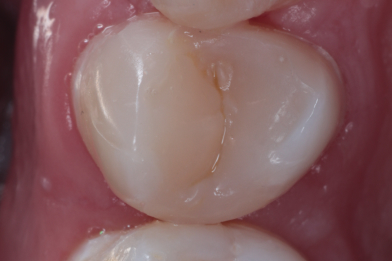

При профилактическом осмотре полости рта у пациента был выявлен кариес 2.6 зуба. Было произведено лечение кариеса с восстановлением анатомической формы зуба.

Бояринов Сергей Эдуардович -